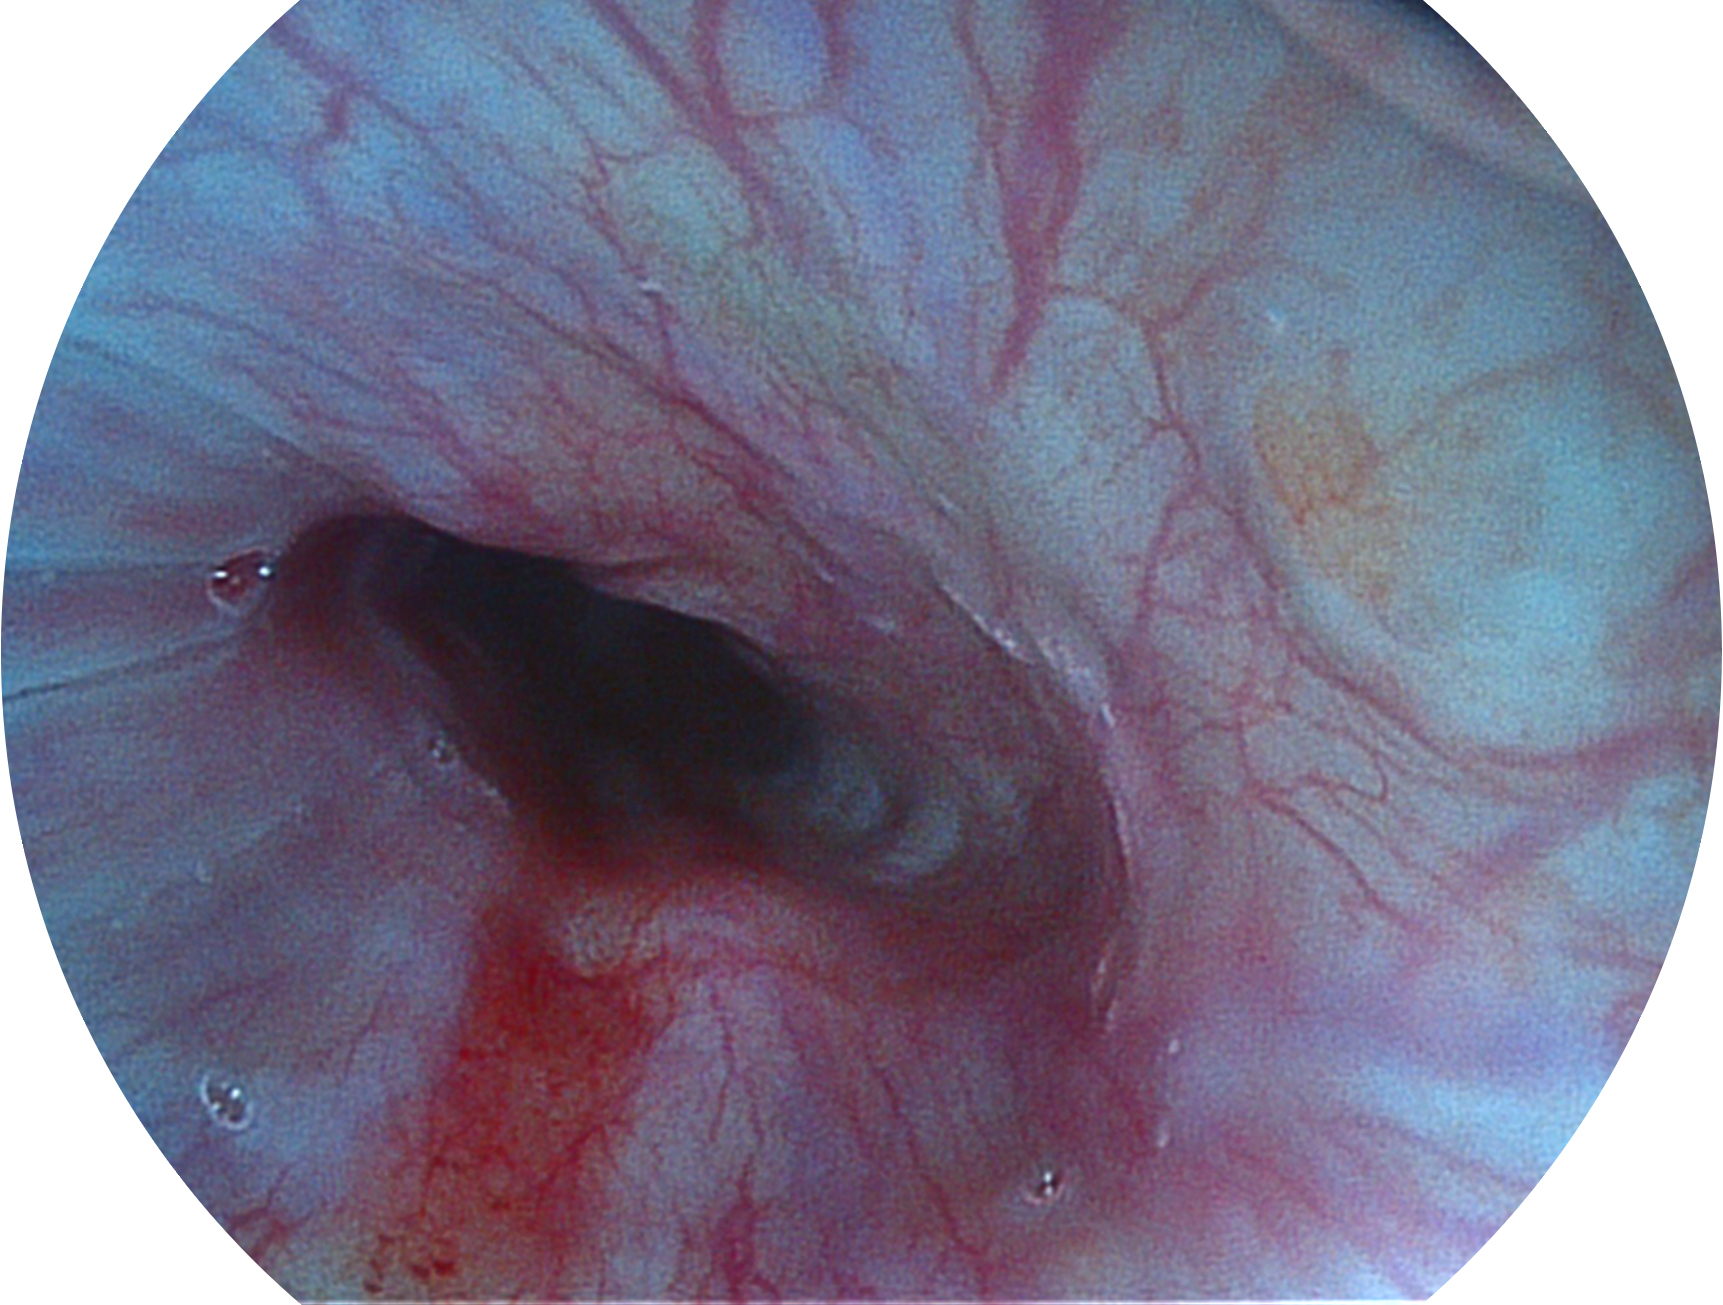

云顶集团官网新开发的内镜染色技术,主要是基于多波长LED 光源的开发,VLS-55Q 四波长LED 光源是由四个不同颜色的LED光按照相应照明模式所规定的特定发光比例进行合束后形成,合束后形成的照明光的光谱由红光、绿光、蓝光及蓝紫光这四个不同的波段范围构成。具有更高光谱自由度,通过光谱比例的控制,实现了聚谱成像技术,英文全称为“Spectral Focused Imaging, SFI”,缩写为“SFI”和光电复合染色成像技术,英文全称为“Versatile Intelligent Staining Technology, VIST”,缩写为“VIST”。